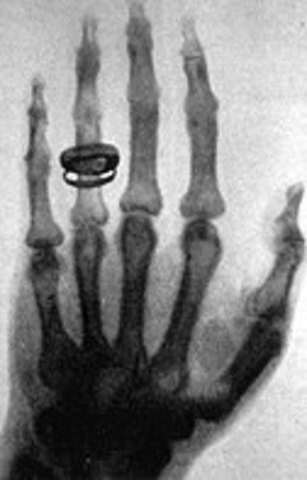

• Rontgen: los rayos X

Rontgen: los rayos X

El físico alemán Wilhelm Conrad Röntgen (1845-1923). Utilizando un tubo de Crookes, fue quien produjo en 1895 la primera radiación electromagnética en las longitudes de onda correspondientes a los actualmente llamados Rayos X. Gracias a su descubrimiento fue galardonado con el primer Premio Nobel de Física en 1901. El premio se concedió oficialmente: "en reconocimiento de los extraordinarios servicios que ha brindado para el descubrimiento de los notables rayos que llevan su nombre.